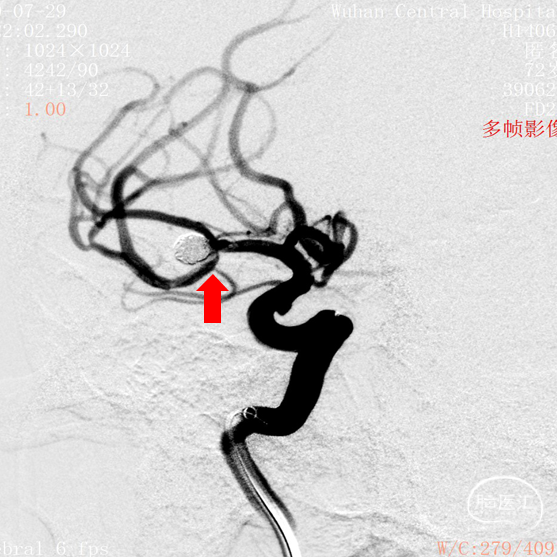

DSA结果:右侧大脑中动脉分叉部动脉瘤,约5.3*5.2mm,颈宽约2.9mm,形态囊状。

术前影像

DSA 2020-07-29

工作角度